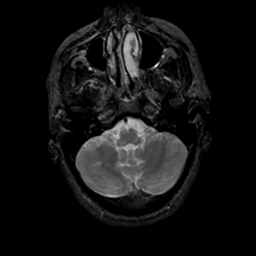

MR Study #18, July 21, 1991 -- Slice #9

[Home][Help][Clinical][Tour 1][Tour 2] Slice 9